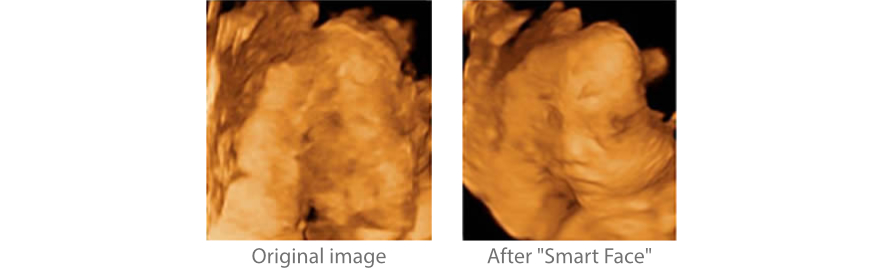

El nuevo Z50 proporciona una optimizaciÃģn rÃĄpida e inteligente del rostro del feto con una simple operaciÃģn de un solo toque. Puede eliminar de forma inmediata las oclusiones en los datos de volumen, excluir el ruido no deseado y generar una visiÃģn Ãģptima del rostro fetal con un mÃnimo de esfuerzo.